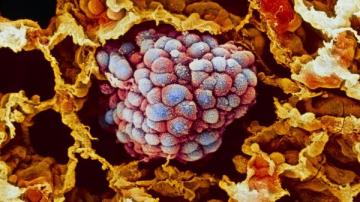

Японские ученые разработали новую программу, которая поможет диагностировать болезни легких

Японские ученые из Медицинского университета Фукусимы и Университета Хиросимы (Hiroshima University) разработали «цифровой стетоскоп». Они создали компьютерную программу, с помощью которой можно анализировать шумы в легких – это помогает поставить верно поставить даже неопытным врачам.

Японские ученые из Медицинского университета Фукусимы и Университета Хиросимы (Hiroshima University) разработали «цифровой стетоскоп». Они создали компьютерную программу, с помощью которой можно анализировать шумы в легких – это помогает поставить верно поставить даже неопытным врачам.Для того, чтобы создать программу для диагностики, ученые во главе с Шиничиро Ошимо предложили медикам поставить диагноз 878 людям – врачам дали прослушать шумы в легких пациентов. Учитывая характерные особенности анализируемых звуков, авторы смогли разработать компьютерную программу для распознавания и классификации шумов.

С помощью такого «цифрового стетоскопа» стало возможно быстро и довольно точно диагностировать различные заболевания легких. Результаты выводились на специальном графике, каждая из пяти осей которого соответствовала одному из пяти типов легочных шумов. Глядя на график, врач видит, для какого заболевания характерны те или иные нарушения.

Получаемые результаты можно было сохранить для дальнейшего анализа или же отправить по электронной почте – это может сделать даже сам пациент. С помощью нового программного обеспечения больные смогут самостоятельно контролировать свое состояние, например, при хронической обструктивной болезни легких или муковисцидозе.